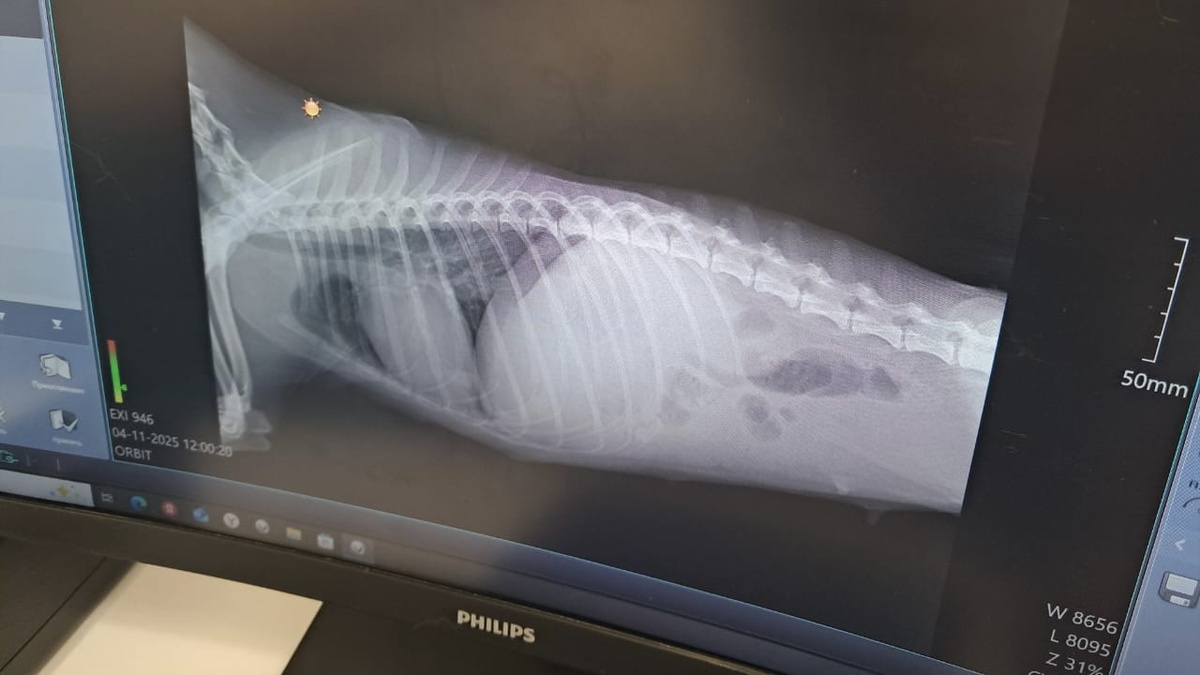

И вот Оливия в клинике. Она такая нежная, милая на этой фотке!

Всё проверили, на всякий случай сделали ещё раз рентген. Челюсть в порядке, рёбра в порядке, просто сильно торчат, потому что собака очень истощена.